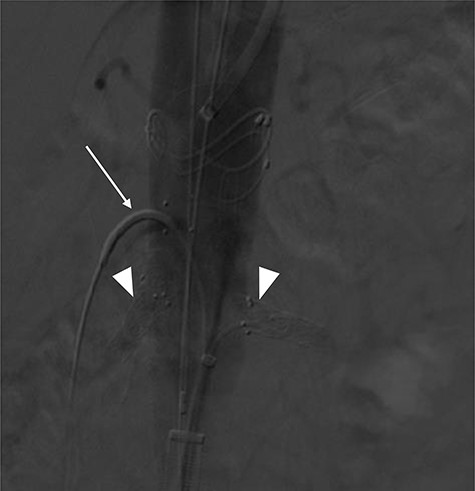

Terumo Aortic Anaconda three-vessel fenestrated and bilateral iliac branched graft was used for repair and was deployed in perirenal position with stents to the SMA and both renal arteries. Surgical arterial access was via left axillary artery (LAA) and percutaneous access was ultrasound-guided via common femoral arteries (CFA) bilaterally. Cannulation of left renal artery (V12 5 × 22 mm) and SMA (V12 9 × 32 mm) was via CFA and right renal artery (V12 5 × 22 mm) was through LAA. There was intra-operative difficulty in SMA cannulation, which was eventually cannulated after repositioning of graft (Fig. 3). Final intra-operative angiogram showed patent renal arteries bilaterally, SMA and common iliac arteries bilaterally (Fig. 4). Post-operatively, he was transferred to surgical high dependency unit (HDU). Three days post FEVAR, he developed abdominal pain, haematemesis and melaena with significantly raised inflammatory markers. CT mesenteric angiogram showed an ischaemic small bowel segment. A necrotic gallbladder was found incidentally during laparotomy, which required cholecystectomy after 20 cm segment of small bowel had been resected and decision was made to not anastomose the small bowel due to the intra-operative findings. A relook laparotomy was performed for small bowel anastomosis and drainage of bile collection found in the gallbladder fossa. Histology results later confirmed infarcted gallbladder with extensive acute inflammation as well as congested, ischaemic and focally infarcted small bowel segment with peritonitis.

Mid-implantation angiogram showing both renal stents deployed (arrowheads) and SMA cannulated (arrow).